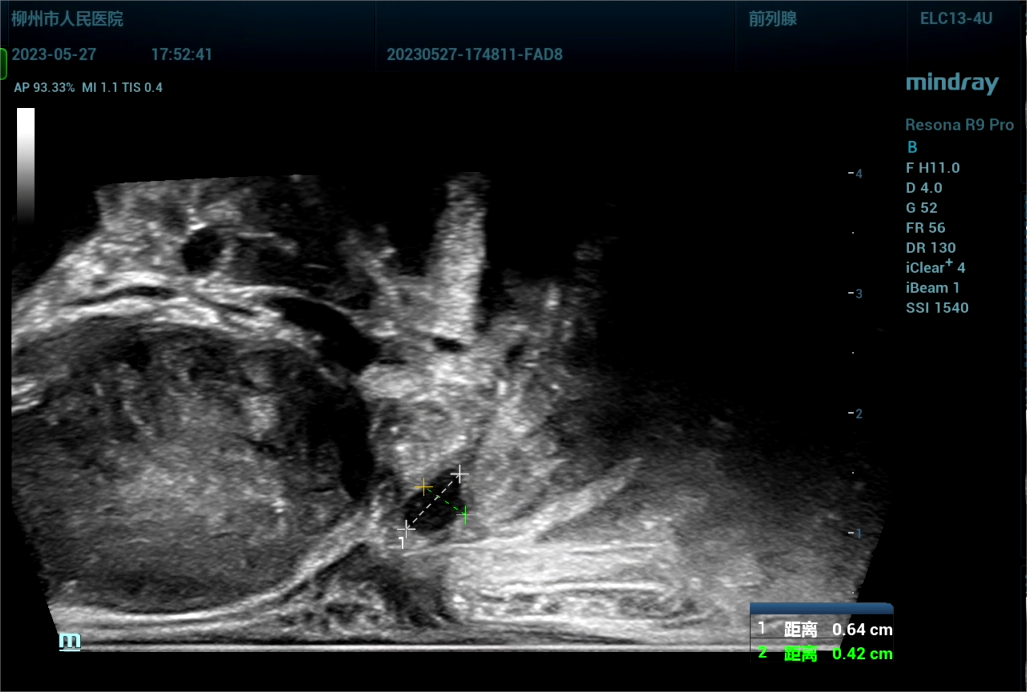

病史为,30岁年轻男性,主诉为反复尿痛2年余。临床诊断是尿路感染。

1686669477070.jpg